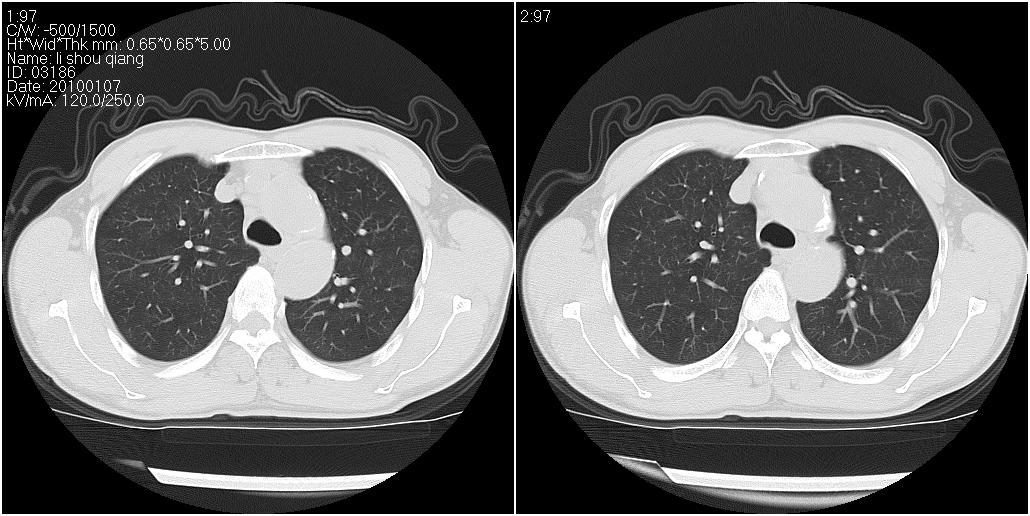

右肺中叶外侧段见一不规则的软组织肿块,边缘可见毛刺,并见厚壁空洞,与胸膜分界欠清。另左下肺见多个小囊状扩张区

右肺中叶外侧段可见团块影,外形不规则,内见空泡征。左下肺见蜂窝状低密度透亮影,部分层面主动脉旁瘤样突出。考虑右肺中叶外围型肺癌可能性大,左下肺支气管扩张,主动脉弓瘤样突出。